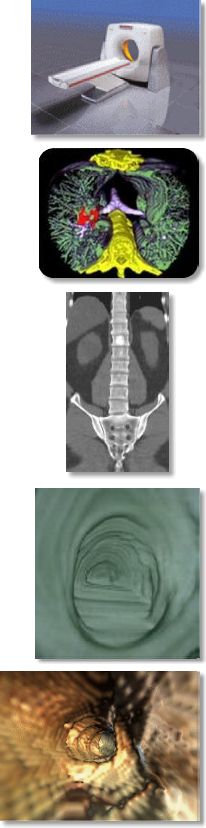

Multi-slice (or multi-detector) CT is a helical or spiral CT scanner with multiple detectors that are capable of scanning several slices simultaneously while in the helical mode, thus significantly increasing scan speed and resolution. The number of detectors ranges from 2 to 16 in the industry depending on the type and price of the scanner, but they all essentially accomplish the same tasks. AIC has a dual-detector MSCT.What are some applications?

- Virtual colonoscopy, bronchoscopy, and endovascular angioscopy

AIC has been offering for some time a screening program called ScanHealth, which includes a screening helical CT of the torso, CT coronary calcium scoring, and more optional 4D virtual colonoscopy (images on the right). Please kindly inform your patients that this program is now offered in their own backyard so they no longer have to travel hundreds of miles to get this test.For more information, please call me personally at (661) 949-8111 and/or visit our website at www.aicLancaster.com.